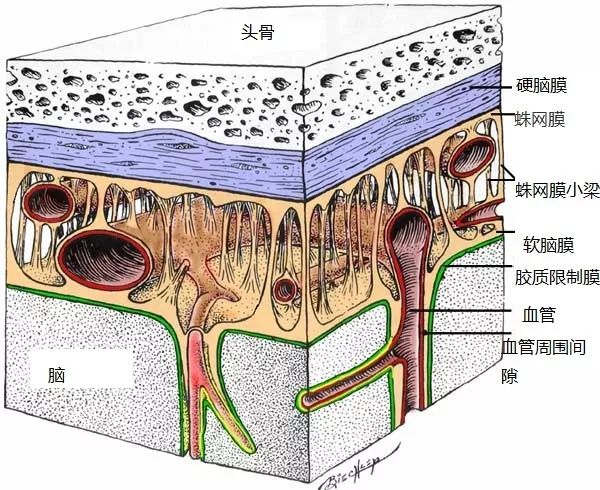

头骨下面,有三层膜包裹着大脑:

最外层的,叫硬脑膜,一层紧实、凹凸不平的防水层。硬脑膜紧贴着头骨。据说,大脑本身不能感知痛觉,但是硬脑膜可以,硬脑膜几乎和脸部的皮肤一样敏感。置于硬脑膜上的压力,或者硬脑膜的瘀伤是很多人头痛的原因。

硬脑膜下面是蛛网膜,是由一层皮和一层结缔组织组成的。我原以为我的脑是漂浮在一些头骨里面的一些液体里面的,然而其实头骨和脑之间唯一的空隙,其实就是蛛网膜的结缔组织间的孔。这些结缔组织使脑不会过多移动,当你的头撞到别的东西时能够起到减震的作用。这些空间里面充满了脊髓液,脊髓液的密度和水相近,所以大脑几乎是漂浮在其中的。

最后一层是软脑膜,一层柔软的和脑外部贴合在一起的皮。当你看到脑的照片的时候,很多时候脑都是被一层恶心的血管包裹住的,而这些血管其实并不是处在脑的表面,而是嵌在软脑膜里面。

下图是一个(应该是)猪头的三层膜的总览:

从左往右,分别是皮肤(粉色部分),然后两层头皮,然后头骨,接着才是硬脑膜、蛛网膜和软脑膜,最右边的是大脑。